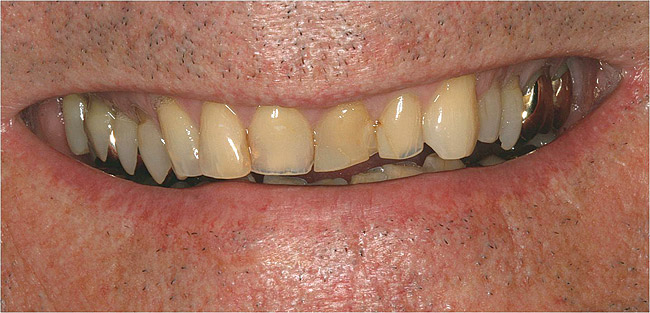

Figure  13   This patient was unhappy with the unesthetic appearance due to tooth surface loss.

Figure 13

Figure  14  Full-mouth rehabilitation with porcelain-fused-to-metal.

Figure 14